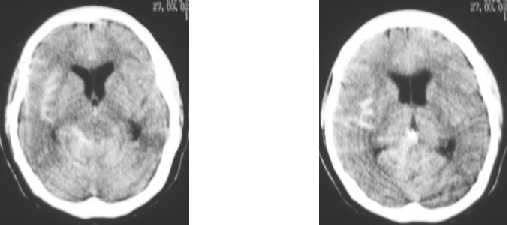

Subarachnoid hemorrhage :